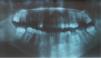

Papillon-Lefèvre syndrome is a rare, autosomal recessive genodermatosis with an estimated prevalence of one to four cases per million people, without sexual or racial predominance.1 It is clinically characterized by diffuse palmaoplantar keratoderma, associated with a severe periodontopathology, with premature loss of deciduous and permanent teeth.1 The cutaneous changes commonly begin during the first four years of life, and the severe destruction of periodontal regions results in loss of the primary teeth within these first four years, as well as premature loss of the permanent teeth.1 The syndrome is caused by a mutation in the gene that encodes the protein cathepsin C, a lysosomal protease known as dipeptidyl-peptidase 1, present in the epithelial regions commonly affected by the syndrome, as well as in cells of the immune system, including polymorphonuclear leukocytes, macrophages and their precursors.1 This case is reported because of the rarity of its pathology and to highlight the importance of the presence of extracutaneous manifestations in diffuse palmoplantar keratodermas, which are often erroneously diagnosed as psoriasis. This case involves a 17-year-old male patient with a history of gingival and periodontal changes since the age of three. The patient mentioned softening and breakage of the teeth, accompanied by halitosis, since the age of eight. In the last three years, exuberant asymptomatic palmoplantar keratoderma has evolved, accompanied by diffuse palmoplantar hyperhydrosis, requiring the continuous use of socks to reduce the discomfort of humidity. He presented a history of multiple hospitalizations for pneumonia and gastroenteritis during infancy, as well as a report of consanguinity. In the dermatological exam, the patient presented accentuated palmoplantar hyperkeratosis on the hands and feet (Figure 1). The oral cavity showed edema and gingival erythema, with bleeding upon manipulation, and the presence of purulent secretion from the lower gingiva (Figure 2). Panoramic radiography of the dental arch revealed areas of alveolar bone loss and ridge resorption (Figure 3). Treatment with acitrentin, emollients and keratolytics was initiated, with satisfactory improvement in the keratoderma and the odontological condition. The palmoplantar keratoderma in Papillon-Lefèvre syndrome typically begins within the first four years of life, with keratotic plaques on the palmar and plantar regions.1,2 Coeli et al. (2008) and Sharma et al. (2013) described cases of this syndrome that presented typical palmoplantar keratoderma in the first year of life, differing from the case described in this report, which presented delayed onset of the cutaneous involvement at 14 years of age.1,2 Severe periodontopathy is the principal oral manifestation of the syndrome, with premature loss of deciduous dentition between the fourth and fifth years of life, and loss of permanent dentition around the fourteenth year. The reported case and the cases described by Coeli et al. (2008) and Kaur et al. (2013) corroborate the early onset of oral manifestations.1–3 In the reported case, the patient presented a history of frequent hospitalizations during infancy for pneumonia and gastroenteritis, which confirms the important susceptibility to infections, described by Liu et al. (2000) and Khan et al. (2012), due to decreased phagocytosis of neutrophils, decreased chemotaxis of leukocytes and peripheral lymphocyte reduction.4,5 The relationship between this genodermatosis and consanguinity is described in 20% to 40% of cases in the literature and is corroborated by the association presented in this case.4,5 The histopathological exam of the lesions is nonspecific, with hyperkeratosis, irregular parakeratosis and moderate perivascular inflammatory infiltrate, the diagnosis being eminently clinical.3–5 Electron microscopy showed vacuoles similar to lipids in the corneocytes and granulocytes, a reduction of tonofilaments and abnormal keratohyalin granules. The cutaneous maifestations are usually treated with keratolytics, emollients and systemic retinoids, with excellent response of the cutaneous lesions and a reduction of edema and gingival erythema, which was proved by the satisfactory therapeutic response in the case reported here and in the cases described by Coeli et al. (2008).1,3,5 The appropriate dermatological treatment, combined with early odontological treatment, is capable of reversing the cutaneous condition, avoiding loss of dentition and, therefore, significantly improving the quality of life of patients.